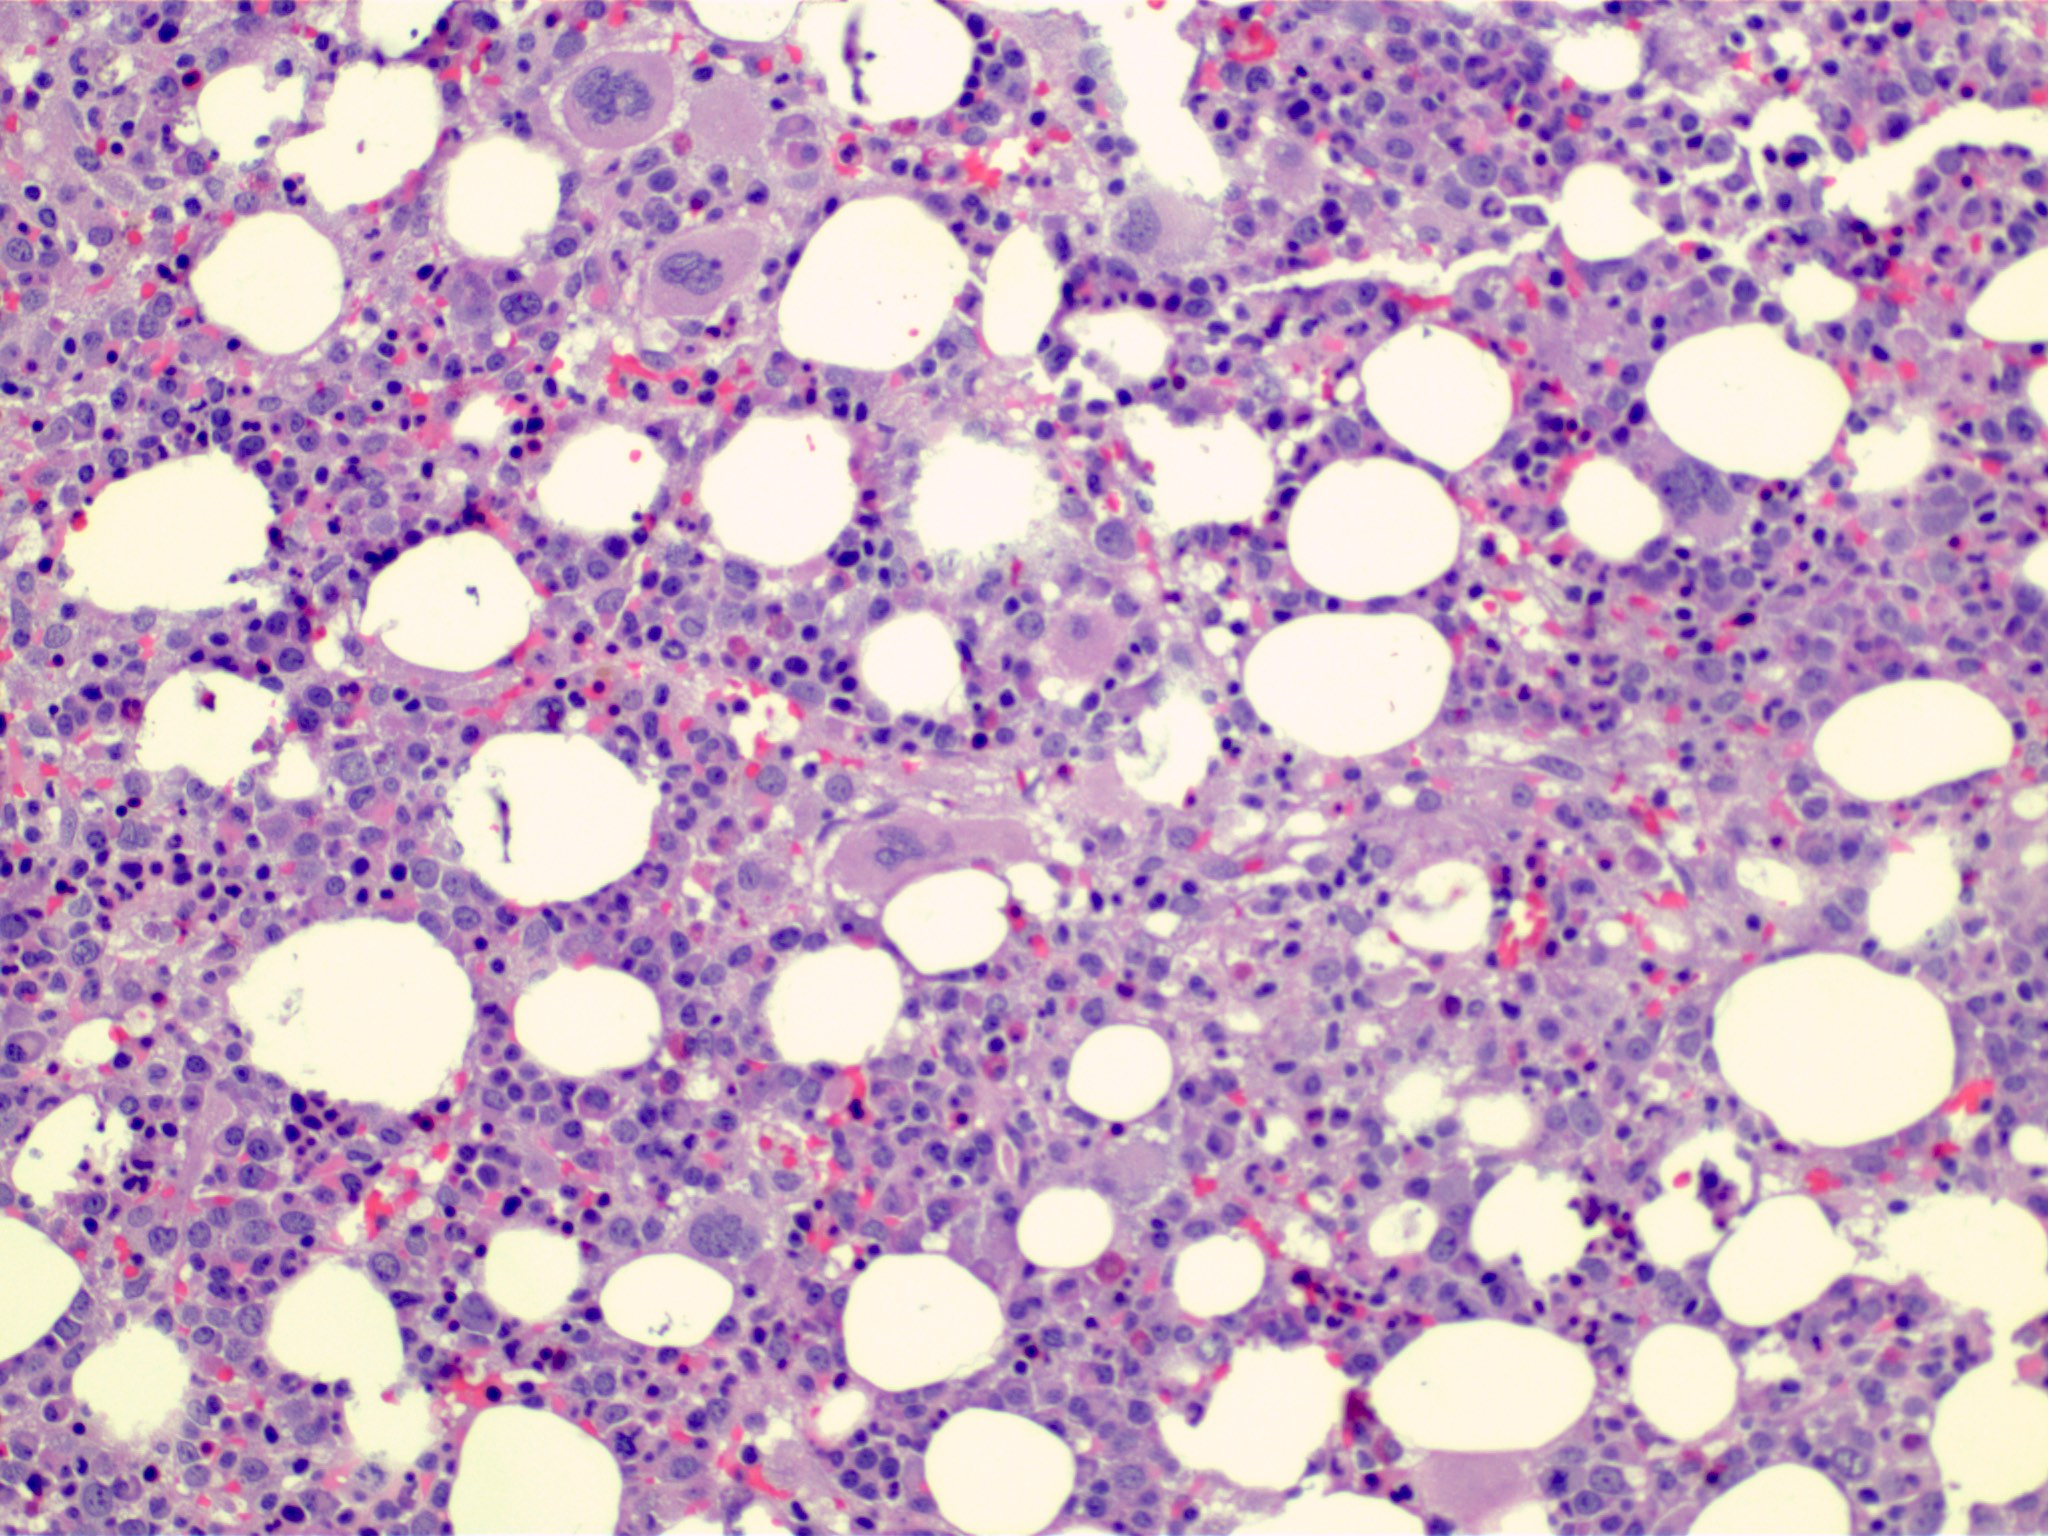

Microscopic (histologic) description

- Bone marrow (Front Oncol 2021;11:778741)

- Dysplasia is seen in at least one hematopoietic lineage

- Percentage of blasts in peripheral blood and bone marrow must be < 20%

- Bone marrow fibrosis is seen in up to 30%

- Increased megakaryocytes with variable clustering

- Often myelodysplasia-like with small size and nuclear hypolobation

- MDS / MPN with iso(17q) typically shows the myelodysplasia-like megakaryocytes

Microscopic (histologic) images